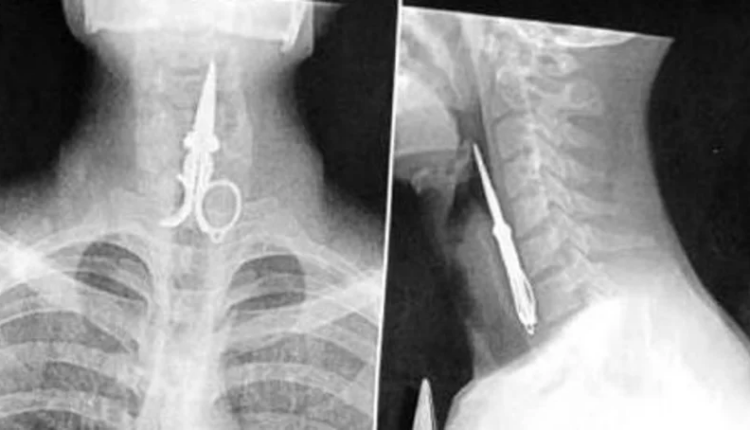

Un interno del Penal de Chimbas, identificado como Axel Hernán Rojas, generó preocupación el lunes por la noche al tragarse la mitad de una tijera en un acto de protesta.

A pesar de su negativa inicial a recibir asistencia médica, Rojas expulsó el objeto por sus propios medios y no requirió intervención quirúrgica. Actualmente, se encuentra fuera de peligro.